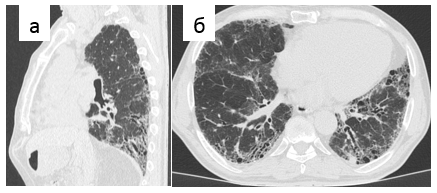

- периферические тракционные бронхо- или бронхиолоэктазы [42] (Рис. 1-3).

Рис. 3. Обычная интерстициальная пневмония, типичная картина. Тракционные бронхоэктазы в кортикальных отделах легких на реформации в косой плоскости (а) и аксиальном срезе (б)